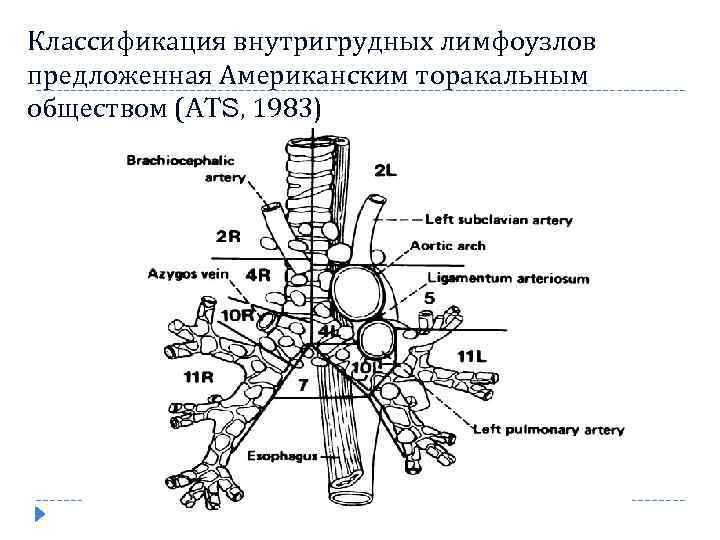

Классификация внутригрудных лимфоузлов предложенная Американским торакальным обществом (ATS, 1983)

Классификация внутригрудных лимфоузлов предложенная Американским торакальным обществом (ATS, 1983)